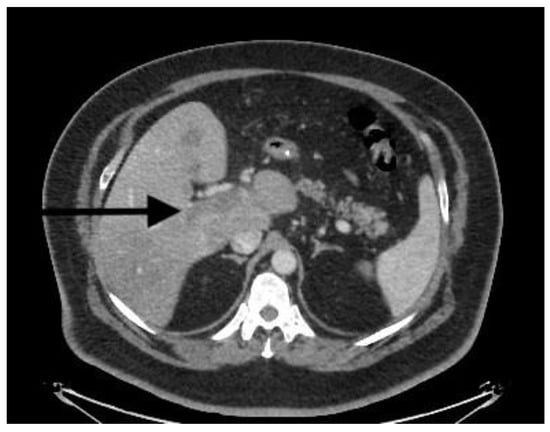

| CT scan | Nonocclusive PVT, posterior right branch, and partial superior mesenteric vein | Nonocclusive PVT, right branch, and partial superior mesenteric vein | Extensive occlusive, portal, splenic, and mesenteric thrombosis; ascites evidence of small-bowel hypoperfusion | Partial PVT |